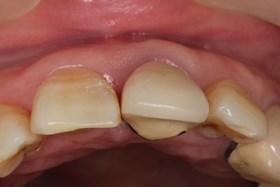

植牙後,立即利用舊牙套轉換成臨時性假牙。

假牙完成後,門牙特寫、切端特寫照,暴牙已不復見